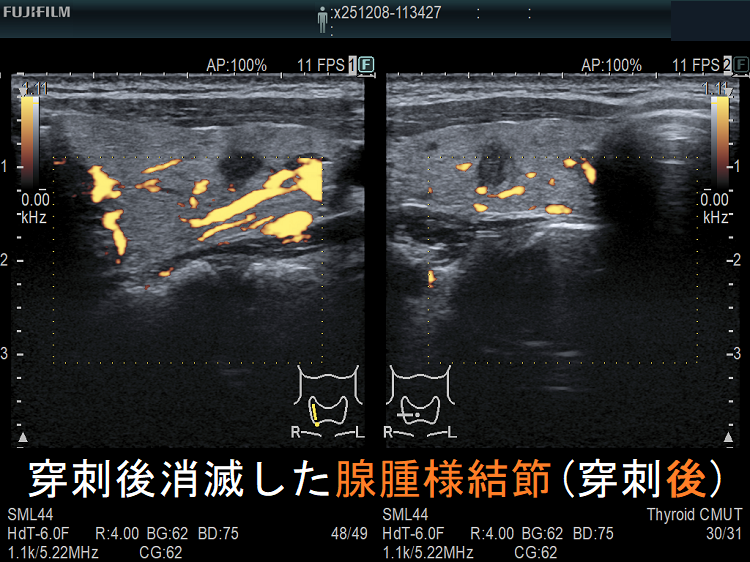

![穿刺後消滅した腺腫様結節(穿刺後) [拡大] 穿刺後消滅した腺腫様結節(穿刺後) [拡大]](../images/basic/basic5/images20251216212323.png)

![穿刺後消滅した腺腫様結節(穿刺後)ドプラーモード[拡大] 穿刺後消滅した腺腫様結節(穿刺後)ドプラーモード[拡大]](../images/basic/basic5/images20251216212330.png)